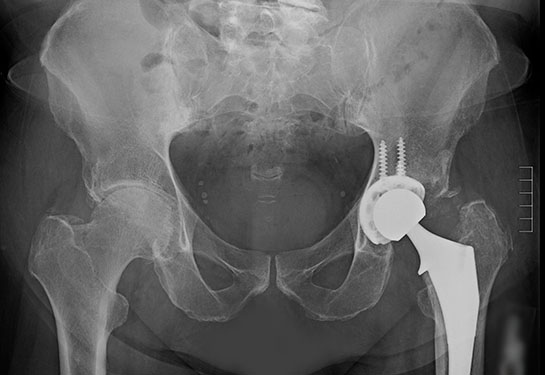

Read MoreMichael McGrath’s complicated medical history caused some surgeons to turn down his request for surgery to restore his mobility. Thanks to a UC Davis Health orthopeadic surgeon, he’s back on his feet.